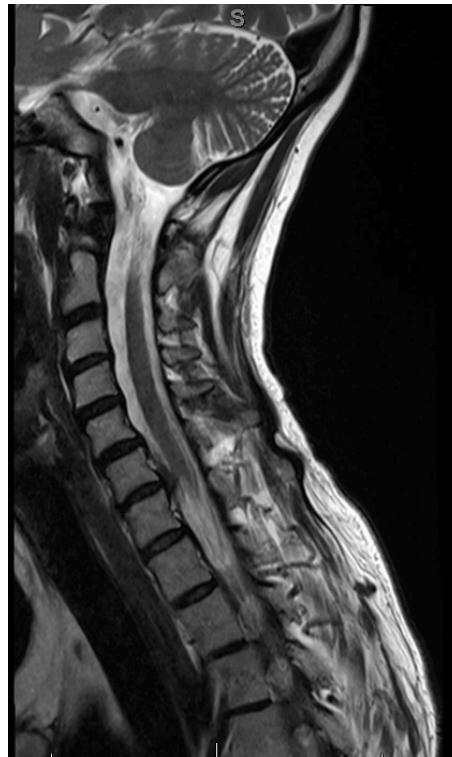

Cervical MyelopathyZ

- Definition: Common form of neurologic impairment caused by compression of cervical spinal cord, most commonly due to degenerative cervical spondylosis

- Typical presentation: Older patients with symmetric numbness and tingling in extremities, hand clumsiness, and gait imbalance

- Treatment: Usually surgical decompression and stabilization as condition is associated with step-wise progression

Imaging:

- MRI: Study of choice to evaluate degree of spinal cord and nerve root compression

Imaging Examples:

Surgical Treatment - Anterior Cervical Discectomy and Fusion: